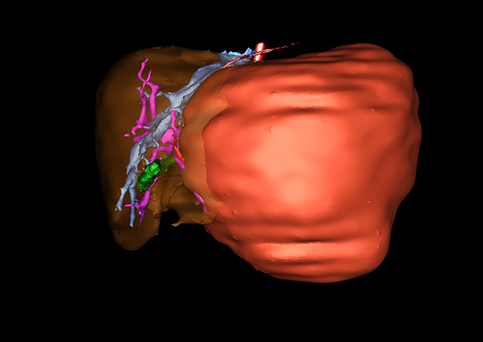

近年来由于数字医学的发展,基于可视化三维重建技术的计算机辅助手术系统极大推进了小儿肝脏肿瘤的精准手术的进步。可以立体透视肝脏解剖、精确掌握肝段的边界、精确测算肝段乃至任意血管所支配的功能体积、准确定位病灶及其与邻近血管的解剖关系,最终对不同手术方案进行比较、筛选和优化。因此,计算机辅助手术规划系统是实现精准肝切除的有力辅助工具,是未来数字外科、精准外科等21世纪外科新理念的重要技术支撑。

计算机辅助手术规划系统具有良好的操作可行性、计算准确性和三维显示效果,可半透明、交互式显示真实的肝内立体解剖关系和空间管道变异,准确计算肝内管道的直径、走行角度,两点间的垂直距离,和任意血管的支配或引流范围等传统二维影像无法获取的信息,有助于实施个体化手术,提高了手术的确定性、预见性和可控性。计算机辅助手术规划系统可直观显示预留肝脏的结构和功能,并可通过虚拟切割功能辅助术者对手术方案进行蹄选和优化,系统评估手术风险和制定对策,改变了部分二维规划的术式和切除范围,使部分二维规划认为不能切除的患者成功手术,提高了手术的根治性、安全性和病变的可切除性,更加符合精准肝脏外科的术前规划要求。详见第11章。

随着计算机技术及影像检查技术的不断发展,以精确的术前影像学和功能评估、精细的手术操作为核心的精准肝切除技术日益受到重视。基于数字医学的计算机辅助手术技术(computer-assisted surgery,CAS)则是实现肝脏精准手术操作的基础。计算机辅助手术系统(CAS)可将术前二维(two dimensional,2D)的CT/MRI影像数据进行三维(three dimensional,3D)重建,建立个体化的肝脏三维解剖模型,清晰显示肝脏内脉管系统的走行及解剖关系,还原病灶与其周围脉管结构的立体解剖构象,准确地对病变进行定位、定性和评估,制定合理、定量的手术方案,实施个体化的肝脏血管取舍分配方案及实施精准肝脏手术。一般认为CAS包括:创建虚拟的患者的图像;患者图像的分析与深度处理;诊断、手术前规划、手术步骤的模拟;术中实时导航。应用本技术后,由于可以更清晰地看出肿瘤的界限,特别是根据肝血管的显影,判断出肿瘤与门静脉及肝静脉的关系以在手术前较准确地估计出手术成功切除的可行性。以往部分根据普通强化CT判断无法手术的病例而被评估为可以成功切除并手术成功。